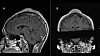

Det viste seg at utveksten bestod av fibrøst vev som lå mellom huden og hodeskallen. MRI-bilder viste også at underhuden var fortykket. Dessuten var selve hodeskallen litt tykkere under klumpen, sammenlignet med områdene rundt.

Før og etter operasjonen. (Illustrasjon: BMJ Case Reports 2024)